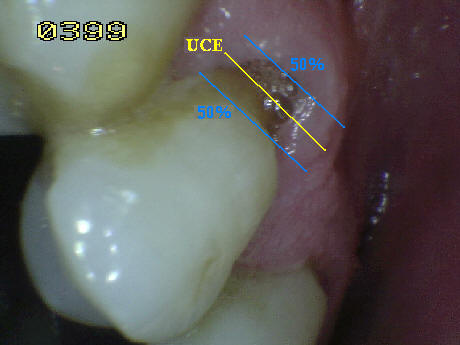

• Cuando la superficie de la corona y la raíz estén afectada por caries deben ser identificadas  independientemente.  En caso de duda porque la lesión de caries se encuentra en la unión cemento-esmalte (UCE)  debe analizarse que superficie esta más afectada o que se  extienda por lo menos 1 mm o más allá del limite de la unión cemento esmalte (UCE), en ambas direcciones cervico-incisal y cervical apical, debe considerase cual es la más extensa aplicando la regla del  50% , si existe igualdad el examinador debe decidir si la lesión es codificada como de raíz o de corona, o en su defecto puede aplicar ambas. Ver imagen derecha.